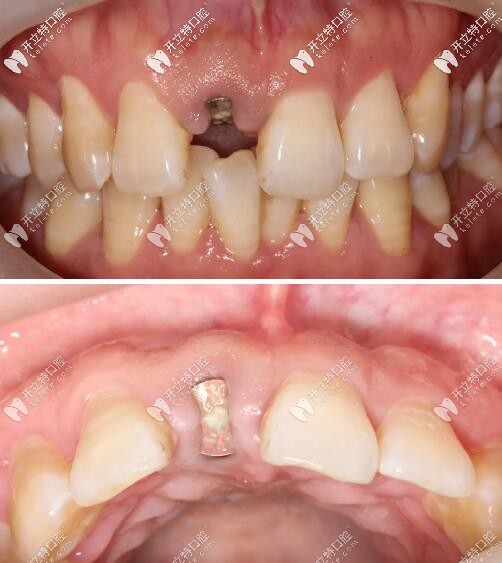

術(shù)后三個(gè)月復(fù)查見近遠(yuǎn)中齦乳頭高度維持良好,唇側(cè)較豐滿。

門牙外傷即刻種植牙三個(gè)月后

三周后戴入全瓷修復(fù)體,紅白美學(xué)效果理想;

門牙瑞士iti鈦親水4.1mm*10mmBL種植體修復(fù)案例

戴牙一年后復(fù)診,口內(nèi)正面觀及側(cè)面像。

門牙磕傷瑞士iti種牙修復(fù)1年后